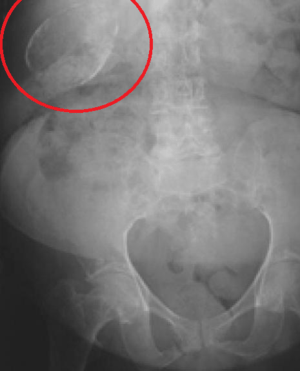

Porcelain gallbladder

Porcelain gallbladder on X-ray | |

Porcelain gallbladder is a calcification of the gallbladder believed to be brought on by excessive gallstones, although the exact cause is not clear. As with gallstone disease in general, this condition occurs predominantly in overweight female patients of middle age. It is a morphological variant of chronic cholecystitis. Inflammatory scarring of the wall, combined with dystrophic calcification within the wall transforms the gallbladder into a porcelain-like vessel. Removal of the gallbladder (cholecystectomy) is the recommended treatment.

Abdominal radiography (X-ray), abdominal ultrasound or CT scan.